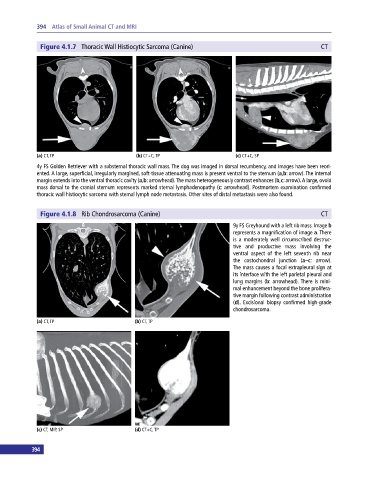

Figure 4.1.7 Thoracic Wall Histiocytic Sarcoma (Canine) CT

(a) CT, TP (b) CT+C, TP (c) CT+C, SP

4y FS Golden Retriever with a substernal thoracic wall mass. The dog was imaged in dorsal recumbency, and images have been reori-

ented. A large, superficial, irregularly margined, soft‐tissue attenuating mass is present ventral to the sternum (a,b: arrow). The internal

margin extends into the ventral thoracic cavity (a,b: arrowhead). The mass heterogeneously contrast enhances (b,c: arrow). A large, ovoid

mass dorsal to the cranial sternum represents marked sternal lymphadenopathy (c: arrowhead). Postmortem examination confirmed

thoracic wall histiocytic sarcoma with sternal lymph node metastasis. Other sites of distal metastasis were also found.

Figure 4.1.8 Rib Chondrosarcoma (Canine) CT

9y FS Greyhound with a left rib mass. Image b

represents a magnification of image a. There

is a moderately well circumscribed destruc-

tive and productive mass involving the

ventral aspect of the left seventh rib near

the costochondral junction (a–c: arrow).

The mass causes a focal extrapleural sign at

its interface with the left parietal pleural and

lung margins (b: arrowhead). There is mini-

mal enhancement beyond the bone prolifera-

tive margin following contrast administration

(d). Excisional biopsy confirmed high‐grade

chondrosarcoma.

(a) CT, TP (b) CT, TP

(c) CT, MIP, SP (d) CT+C, TP